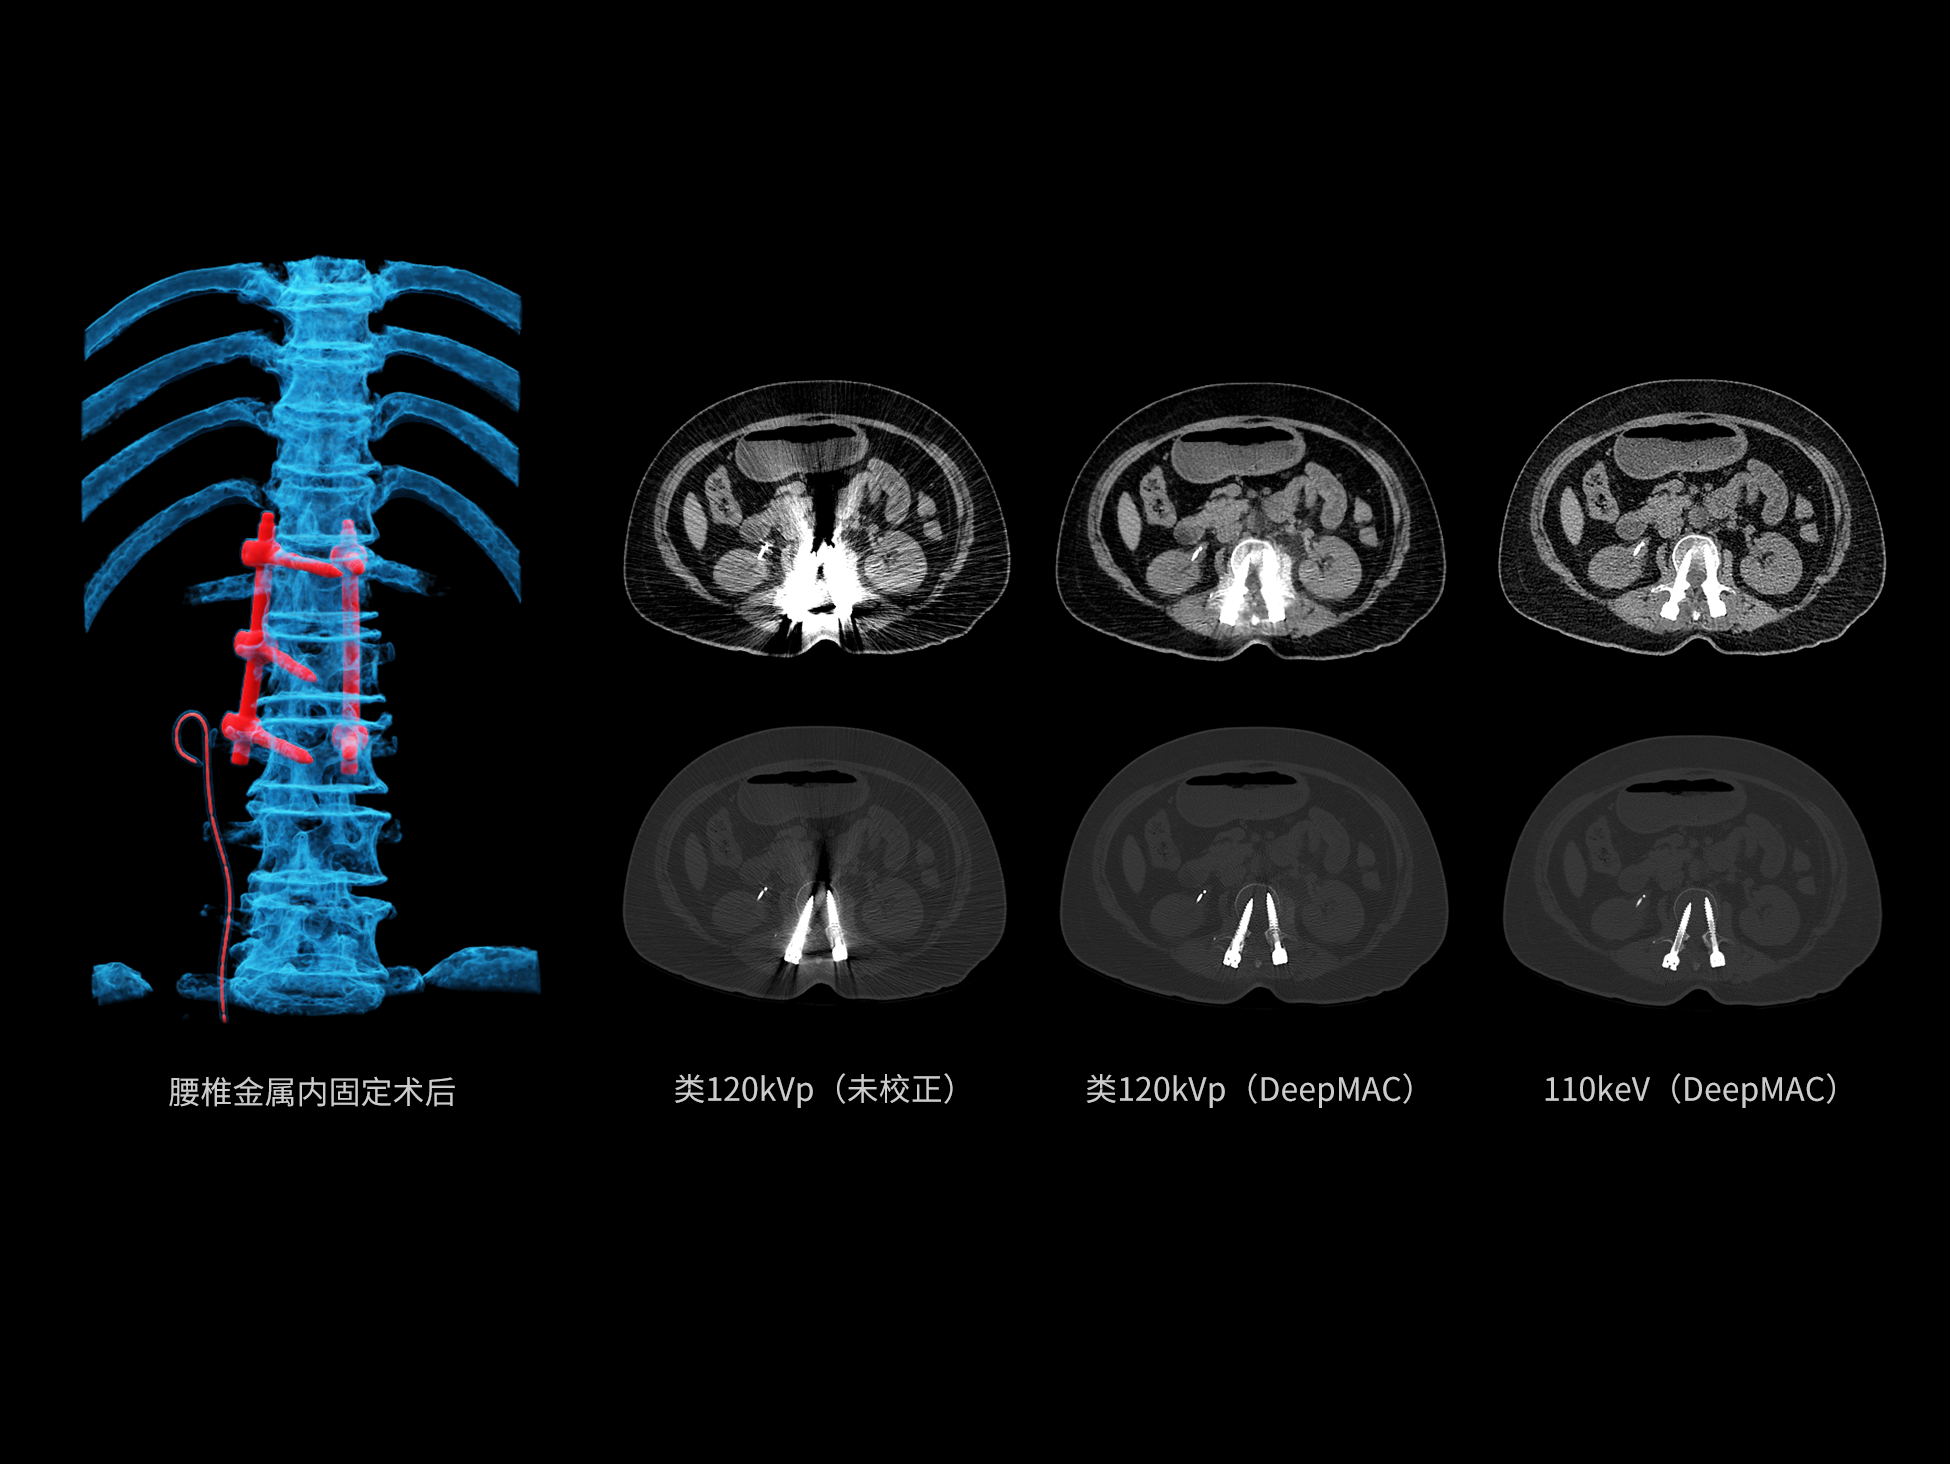

• 双能高精配准与硬化伪影校正

• 高清能谱分解&降噪重建技术

uCT SiriuX® 依托16cm超宽探测器与双源能谱技术,实现真正意义上的全身高清能谱成像。单次扫描同步获取灌注、能谱等多维定量参数,精准解析组织特性与病灶成分,为临床决策提供更深层次的诊断依据。

能谱成像可揭示丰富的物质与能量信息,其临床价值的充分释放有赖于完善高效的后处理分析平台。uCT SiriuX® 提供全面能谱高级分析工具,覆盖心血管、肿瘤、神经、骨科等多类临床场景。平台支持动脉增强分数分析(AEF)、细胞外容积分析(ECV)、肿瘤同源性分析、肺栓塞分析、骨髓水肿分析等多项评估,并提供多达10种基物质对成像,为精准诊断与科研探索提供坚实支撑。